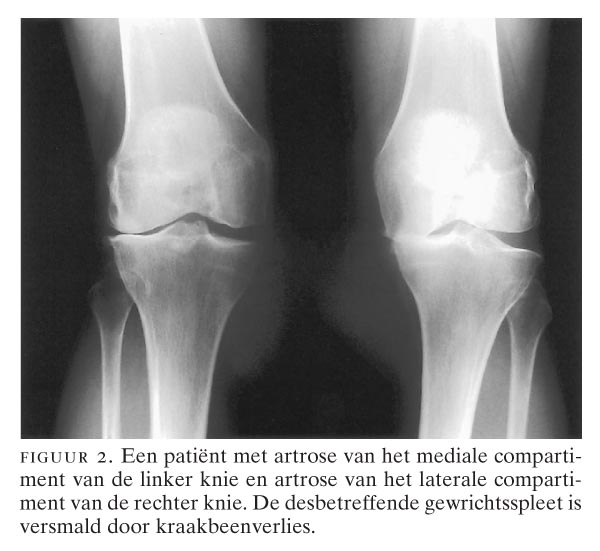

Bot Op Bot Knie. Osteotomie ter hoogte van de knie voor jonge patiënten met gonartrose NTVG Artrose aan de knie wordt ook wel gonartrose genoemd Hierdoor wordt de ruimte tussen de botten kleiner en kan er bot-op-botcontact ontstaan

De verdunning van het kraakbeen wordt opgedeeld in verschillende graden van lichte graad (graad 1: verdunning/uitrafeling van kraakbeen) tot volledige slijtage (graad 4: geen kraakbeen meer aanwezig, zogenaamd bot-op-bot contact) Dat zorgt voor pijn en kan zelfs een hoorbaar krakend geluid veroorzaken Dat betekent dat hij sneller vervangen moeten worden dan op oudere leeftijd